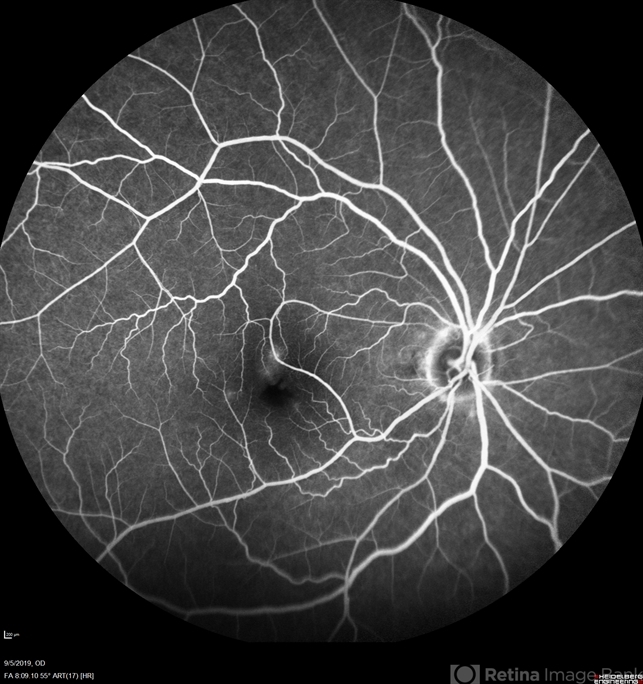

- retinal arterial macroaneurysm

- Retinal arterial macroaneurism.